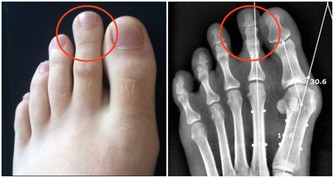

2、骨關節病

粗鹽熱敷4個部位治好4大頑疾可惜很少有人會用

與骨關節相關的風、寒、濕、痺、痛、關節僵硬等症,如頸椎病、肩周炎、風寒引起的風濕炎症和疼痛。

將粗鹽熱敷包裹在疼痛、怕冷的關節部位,每次熱敷20-40分鐘,至粗鹽逐漸冷卻即可。

“對於重度患者來說,只能輔助治療,不能完全取代藥物、手術等,應儘早就醫,以免耽誤治療最佳時機。